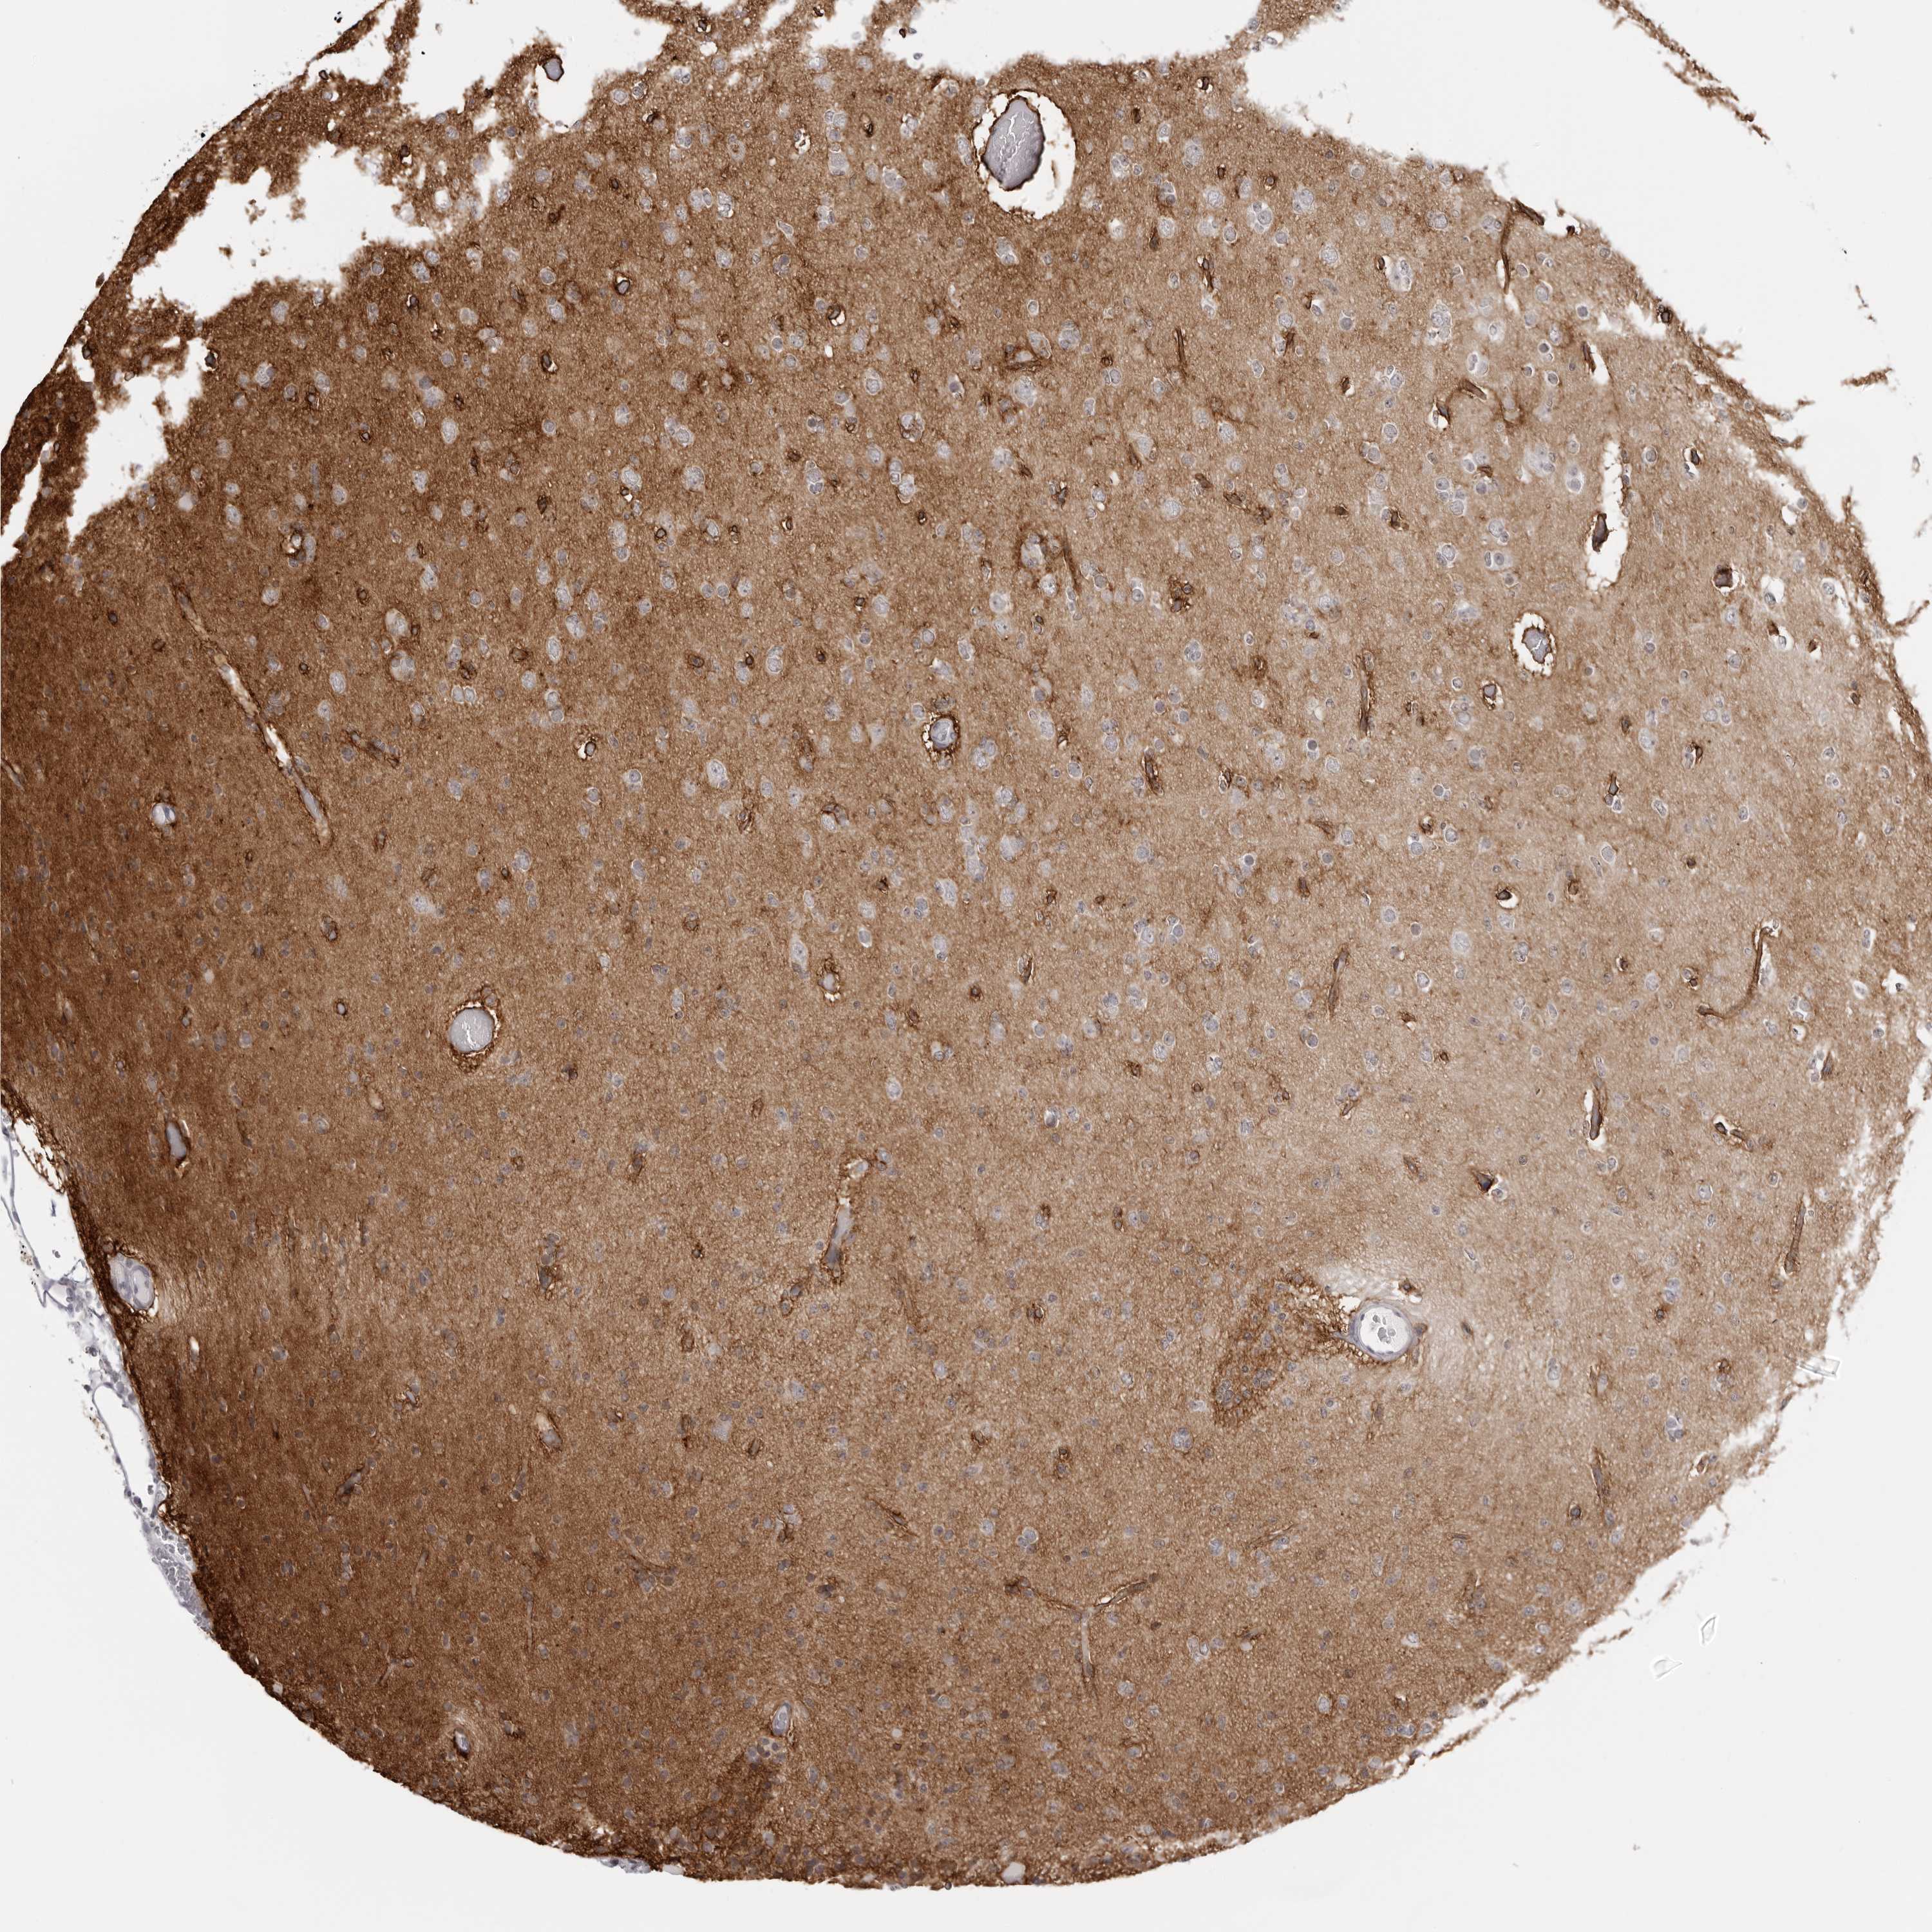

GLIOMA - Protein expressioni

A mouse-over function shows sample information and annotation data. Click on an image to view it in a full screen mode. Samples can be filtered based on level of antibody staining by selecting one or several of the following categories: high, medium, low and not detected. The assay and annotation is described here.

Note that samples used for immunohistochemistry by the Human Protein Atlas do not correspond to samples in the TCGA dataset.

Antibody stainingi

Antibody staining in the annotated cell types in the current human tissue is reported as not detected, low, medium, or high, based on conventional immunohistochemistry profiling in selected tissues. This score is based on the combination of the staining intensity and fraction of stained cells.

Each image is clickable and will lead to virtual microscopy that enables deeper exploration of all samples and also displays staining intensity scores, fraction scores and subcellular localization as well as patient and tissue information for each sample.

Antibody HPA028411

Staining

High

Medium

Low

Not detected

Intensity

Strong

Moderate

Weak

Negative

Quantity

>75%

75%-25%

<25%

None

Location

Nuclear

Cytoplasmic/membranous

Cytoplasmic/membranous,nuclear

Glioma, malignant, High grade

Glioma, malignant, Low grade